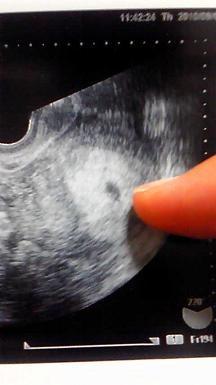

期待しすぎないよう、でもドキドキしながら病院へ。先生に超音波画面を向けられ「妊娠していますよ、ほらココに、ね」と告げられた瞬間(内診の姿で・・・)大泣きしてしまいました。